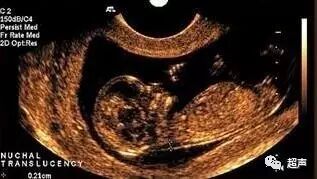

NT检查属于影像学检查,一旦NT异常,那么有1/6的可能胎儿是染色体异常。唐氏筛查属于血清学检查,一旦提示高危,那么所有提示高危里面会有2.5%的胎儿染色体异常,两个并不具备直接可比性,但如果两项检查联合起来,准确率可以达到90%以上,所以联合起来使用效果更佳。

NT检查不像唐筛一样提示高危低危,如果NT大于3mm,那么意味着胎儿有1/6额可能是染色体异常,目前推荐是做羊水穿刺,也就是绒毛取样检查,如确定染色体异常,尽早处理,但羊水穿刺有一定的风险,且技术难度较高,所以很多孕妈妈还是会在晚一些进行羊水穿刺检查胎儿染色体而不会再行唐筛。

那么如果NT小于3mm,意味着发生胎儿染色体风险很小,就像上面一个问题介绍的,如果能再行唐筛检查,可以进一步降低胎儿染色体异常的风险,目前有些地区开展了早期唐筛,就是NT结合11到14周的血清学检查,这个检查准确性更高,如果进行了早期唐筛,就不必再进行中妊期唐筛了。